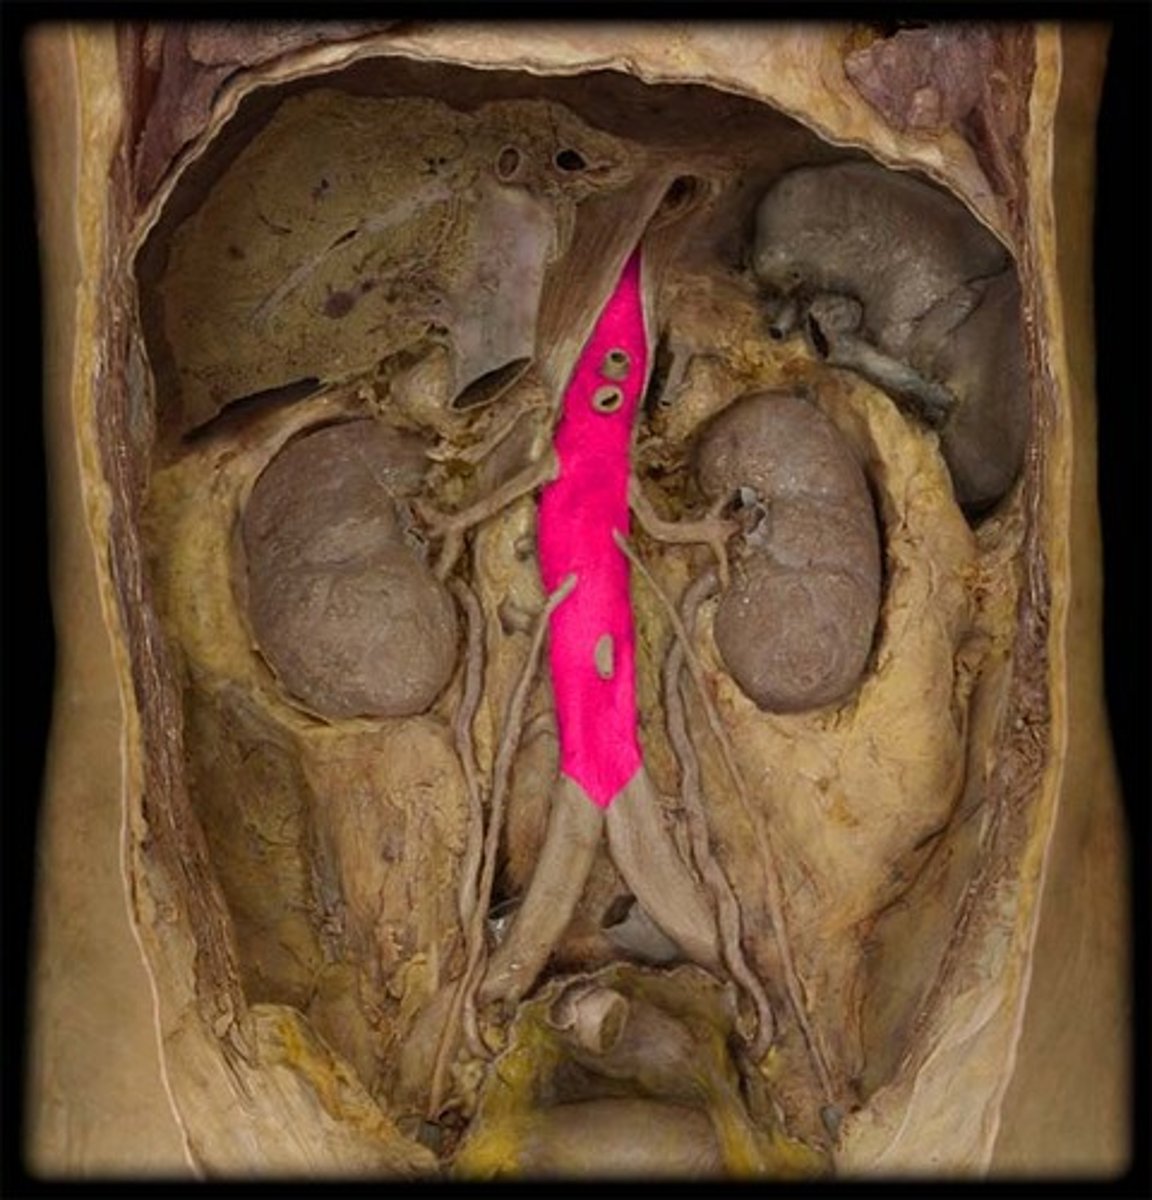

Abdominal aorta

portion. the tube!

right renal arteries

the right is on top. we have to flip the kidney.

left renal arteries

below the kidney for left.